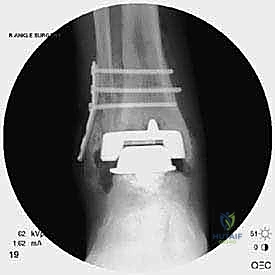

مراجعة مفصل الكاحل الصناعي هي إجراء جراحي ضروري لمعالجة المشاكل التي قد تنشأ بعد الجراحة الأولية، مثل كسور الكعبين أو عدم استقرار المفصل. يتضمن العلاج التشخيص الدقيق عبر الأشعة السينية والتصوير المقطعي، يليه التدخل الجراحي لتثبيت الكسور واستعادة وظيفة الكاحل، مع التركيز على التعافي المبكر.

تُعد جراحة مراجعة مفصل الكاحل الصناعي (Revision Total Ankle Replacement) من الإجراءات الجراحية المتقدمة والبالغة الدقة في عالم جراحة العظام الحديثة. لا تقتصر هذه الجراحة على مجرد استبدال مفصل تالف بآخر جديد، بل هي عملية إنقاذ معقدة للغاية تهدف إلى معالجة المشاكل الميكانيكية والبيولوجية التي تنشأ بعد الجراحة الأولية. من أبرز هذه المشاكل: الفشل الميكانيكي للمفصل، تحلل العظام (Osteolysis)، أو حدوث كسور معقدة في الكعبين (Malleolar Fractures) المحيطة بالمفصل الصناعي. يتطلب هذا الإجراء تقييماً سريرياً وشعاعياً دقيقاً يشمل التصوير المقطعي ثلاثي الأبعاد والأشعة السينية، يليه تدخل جراحي دقيق لاستعادة التوازن الحيوي والميكانيكي للكاحل والحفاظ على الطرف من البتر أو الدمج.

الخطوة الخامسة: تركيب المفصل الجديد أو الدمج

يتم إدخال المفصل الجديد المخصص للمراجعة، والذي يحتوي غالباً على سيقان (Stems) تدخل عميقاً في عظمة الساق وعظمة الكاحل لضمان الثبات الميكانيكي. في حال وجود كسور في الكعب، يتم تثبيتها في هذه المرحلة.

يتم خياطة الأربطة والأنسجة الرخوة والجلد بطرق تجميلية دقيقة لتقليل الندبات وسرعة الالتئام، ثم توضع القدم في جبيرة خلفية واقية.